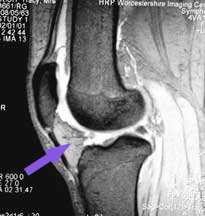

The arrow shows you the undersurface of the patella. You can see how it only its undersurface projects into the joint cavity (white). Any idea what that triangular grey mass is which is projecting into the knee joint below the patella?

Did you get it? If so, well done. It is the fat pad.

From the point of view of arthroscopy, it is important to know that the joint cavity extends upwards, a handsbreadth above the patella, into a pocket called the 'suprapatellar pouch' - literally 'the pouch above the patella'. You can see this pocket in these MRI scans (white colour in this view). Surgeons often fail to fully examine this area, particularly with the arthroscope above the patella, and problems can be missed.